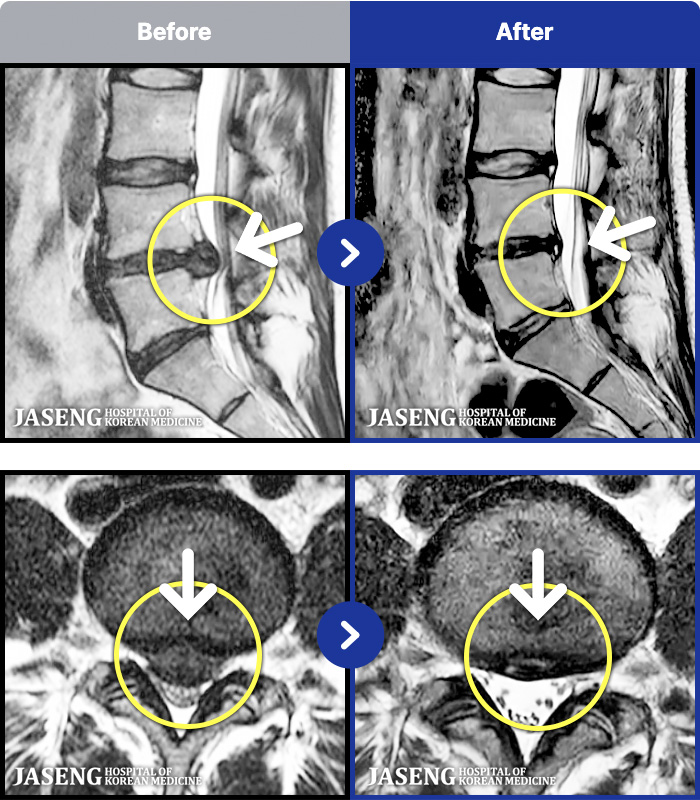

- MRI ġ

MRI ġ

1,237 MRI ũ ʸ Ȯϼ.